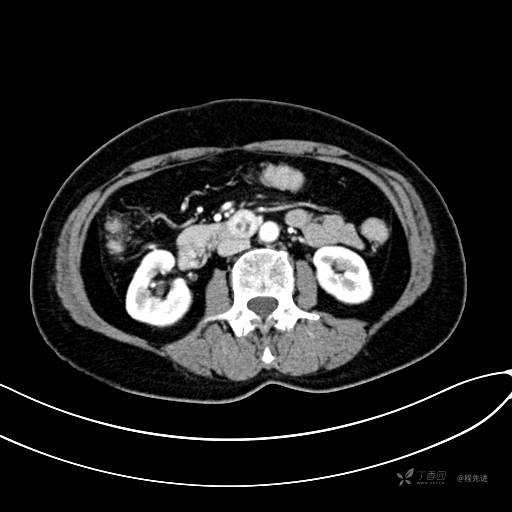

CT增强动脉期